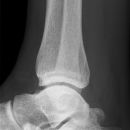

Sprunggelenk

Weber A

Es wurden keine Bilder gefunden.

Weber B

Weber C + dorsales Volkmann

Trimalleoläre

Vorderes Volkmann + lat. Talusschulter